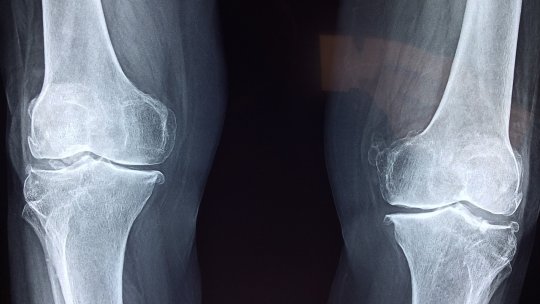

Meniscurile sunt mici discuri cartilaginoase situate în articulația genunchiului, intercalate între femur în partea...

Genunchiul este o articulație complexă care combină os (femur, tibie, fibulă, rotulă), cartilaj (suprafețe articulare și...